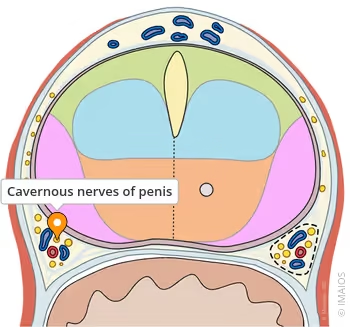

penile nervous system.

Yes. There is a network of nerves inside the penis — nerves that function like electrical wires.

And it is these nerves that send the signal that makes an erection happen.

If the nerves are strong → an erection happens naturally.

If the nerves are weak → the erection fails.

If the nerves are damaged → the erection disappears.

WHY NERVES CONTROL EVERYTHING (AND WHY NO ONE TOLD YOU THIS)

An erection happens in three stages:

⦁ The brain sends the nerve signal.

⦁ The penile nerves receive and amplify this signal.

⦁ The penis reacts with blood, rigidity, and expansion.

Simple.

But here’s the detail that changes everything:

If step 2 fails…

Step 3 never happens.

And this is exactly where 90% of men with ED are failing.

Blood only responds to nerves.

No nerves = no erection.

During his studies on peripheral neuropathies (nerve damage), Dr. Mercer noticed that many patients — especially men over 50 — had exactly the same type of nerve degeneration in the pelvic region.

“Nerve degeneration in the penis is one of the first detectable signs of silent neuropathy in older men. It is not disease. It is not age. It is accumulated damage.”

…it meant that the penis had one of the most sensitive nervous systems in the male body.

A direct penile neurostimulation module — portable, safe, and calibrated with millimetre-level precision for the unique sensitivity of the cavernous nerves.

1) Recruitment of dormant fibres — Nerves that are not dead may have fibres with a high activation threshold. The appropriate stimulus reduces this threshold, causing lost fibres to participate in conduction again.

2) Localised neural plasticity — Repeated neurostimulation induces adaptive changes in the synapse: increased local neurotransmitters, greater sensitivity of the endings, and functional remodelling that supports persistent communication between the brain and the penis.

3) Peripheral reflex modulation — In addition to reactivating the pathway, the stimulus optimises the local reflex (the so-called pelvic reflex arc), which allows simple sensory stimuli to trigger more robust erectile responses.